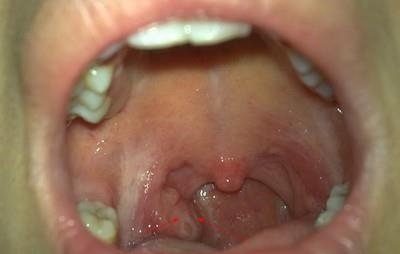

腭扁桃体是一对扁卵圆形的淋巴器官,位于扁桃体窝内。扁桃体窝:口咽外侧壁在腭咽弓和腭舌弓之间的三角形凹陷。粘膜上皮向实质内下陷形成不陷窝,称扁桃体小窝。扁桃体前下部分被子腭舌弓遮盖,其上端未被覆盖的部分由结缔组织构成的扁桃体体囊包绕,此囊仅借疏松结缔组织与咽肌相连。此处常是扁桃体周围脓肿形成部位。咽淋巴环由腭扁桃体、咽扁桃体、咽鼓管扁桃体、舌扁桃体组成。扁桃体发炎怎么办?

以腭扁桃体最大,通常所说的扁桃体即指腭扁桃体。腭扁桃体有一对,位于舌腭弓与咽腭弓之间,卵圆形,表面为复层鳞状上皮所覆盖。上皮向扁桃体内部陷入形成10~20个隐窝,隐窝中含有脱落的上皮细胞。淋巴细胞及细菌等。上皮下方及隐窝周围密集分布着淋巴小结及弥散淋巴组织,淋巴细胞常穿过上皮而沉积于口咽部。扁桃体的被膜是一层致密的结缔组织,它把腭扁桃体与邻近器官隔开,有阻止腭扁桃体感染扩散的屏障作用。

1、急性卡他性扁桃体炎:病变较轻,炎症仅限于表面粘膜,隐窝内及扁桃体实质无明显炎症改变。可有咽痛,低热,疲劳,食欲欠佳等,局部表现咽痛,见扁桃体及舌腭弓、咽腭弓充血、水肿,扁桃体不明显肿大,表面无明显渗出物。

2、急性化脓性扁桃体炎:炎症从扁桃体隐窝开始,很快进入扁桃体实质,因此扁桃体明显肿大,隐窝内充满脱落上皮、脓细胞、细菌等渗出物,严重时化脓。发病很急,全身症状重,发热,畏寒,食欲不振,体温可升至38℃~40℃,局部表现咽痛明显,甚至饮食、语言困难,咽痛可向耳部放射,有时感到转头不便,下颌角淋巴结肿大。幼儿高热可引起呕吐,抽搐,昏睡。

3、慢性扁桃体炎:局部多无明显自觉症状,时有咽干、异物感、发痒等,常有急性发作史。儿童扁桃体过度肥大可影响呼吸和吞咽。若腺样体也大时,则致鼻堵、打鼾。因小窝内细菌及毒素吸收,可致头痛、乏力及低热等。了解这些扁桃体炎的典型表现,对于患者及时意识到自身疾病,及时治疗很有帮助。